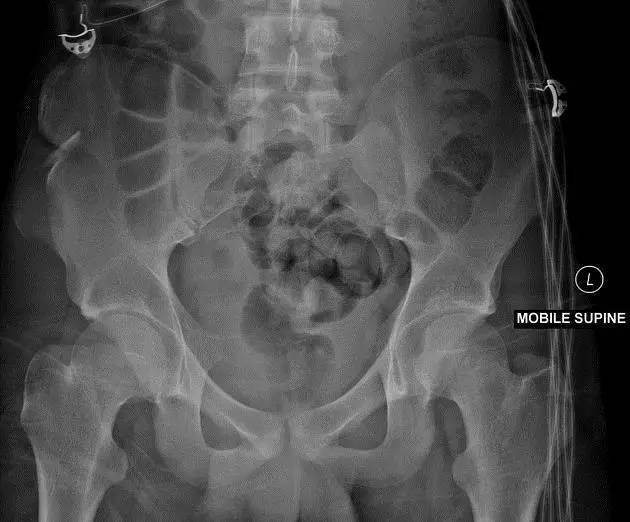

2. Malgaigne 骨折(bucket handle 骨折,即桶柄骨折)

不稳定性骨盆骨折伴有前方和后方的骨折线累及髋关节。

(来源:radiopaedia)